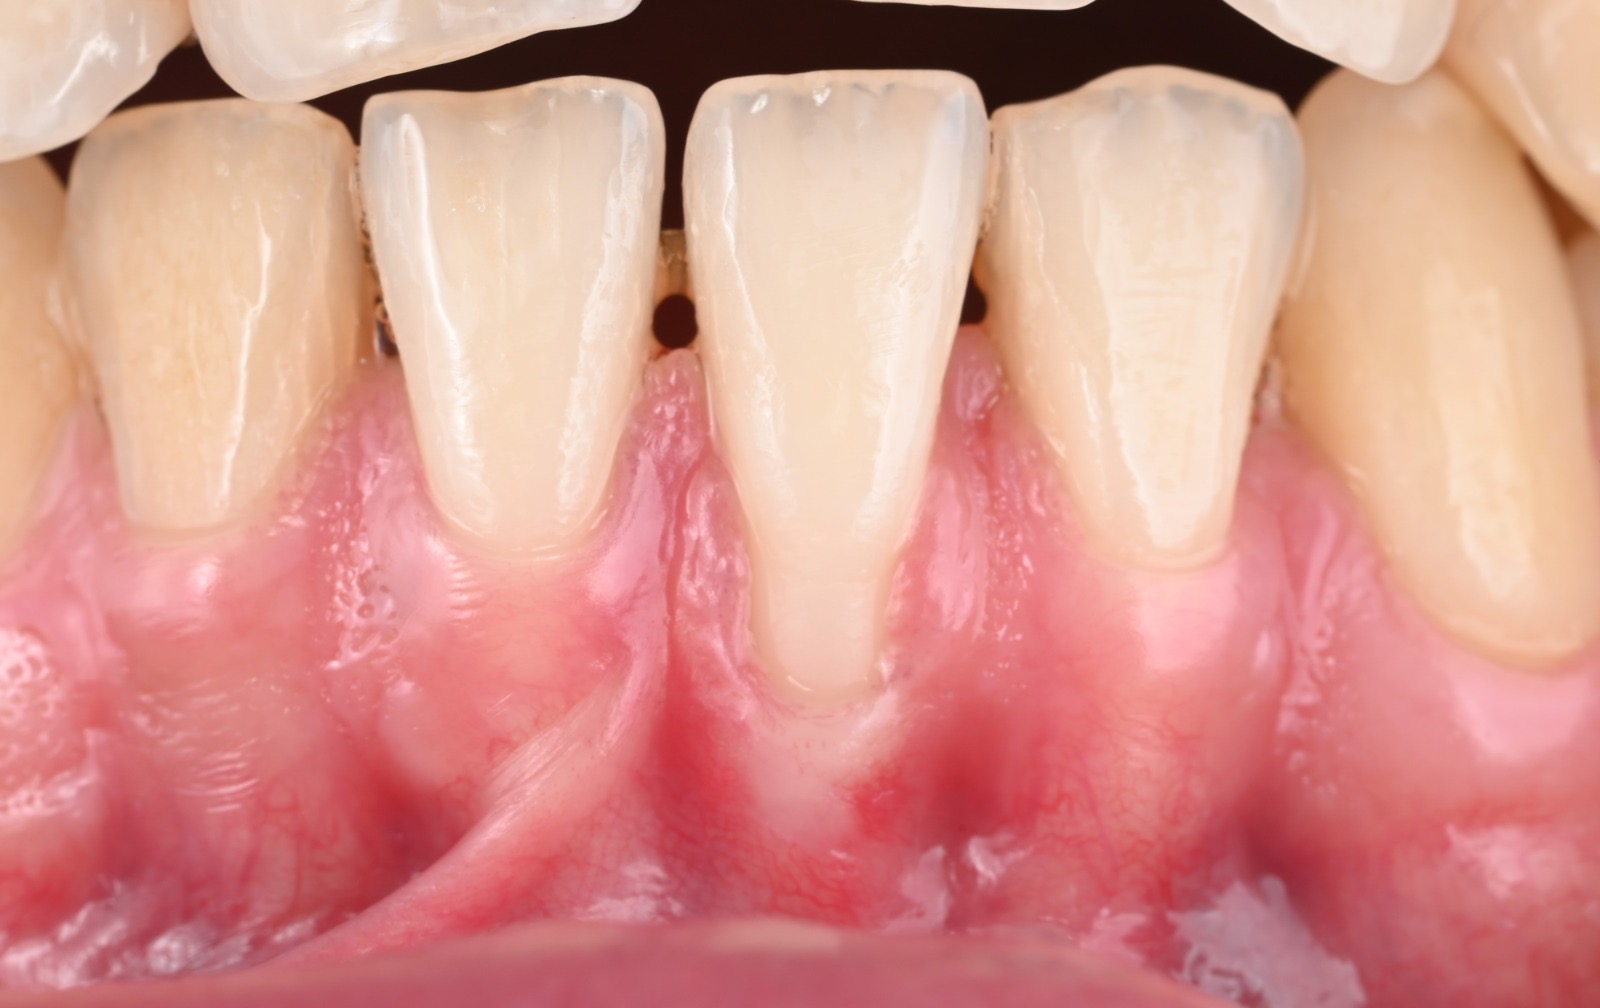

Après

After